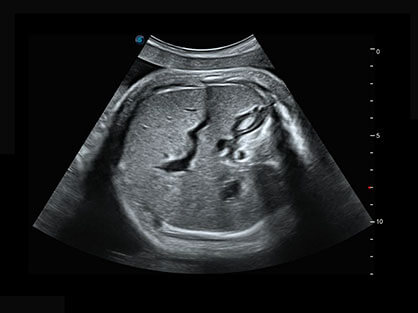

自动获取标准切面,自动完成测量,帮助医生快速完成检查,同时提升测量准确性。

宽频带腹部凸阵探头和腹部容积探头、大角度腔内探头和腔内容积探头、独特的生殖专用曲柄探头,为妇产应用提供全面诊疗方案。

卵泡结构的自动识别和测量,可显示多组测量数据。

大角度腔内容积探头,可完整包络子宫及盆底结构,充分展示组织结构毗邻关系。